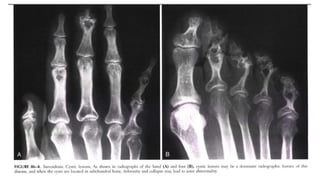

 Highly probable sarcoid arthritis includes the typical features of the

trabecular pattern, osteolysis, cyst formation, and punched-out lesions

Subcutaneous nodules. Observe the prominent

soft tissue nodules in the second and third

digits, with acro-osteolysis of the terminal

tufts.

 Highly probablesarcoid arthritis includes the typical features of the trabecular pattern, osteolysis, cyst formation, and punched-out lesions

Subcutaneous nodules. Observethe prominent soft tissue nodules in the second and third digits, with acro-osteolysis of the terminal tufts.